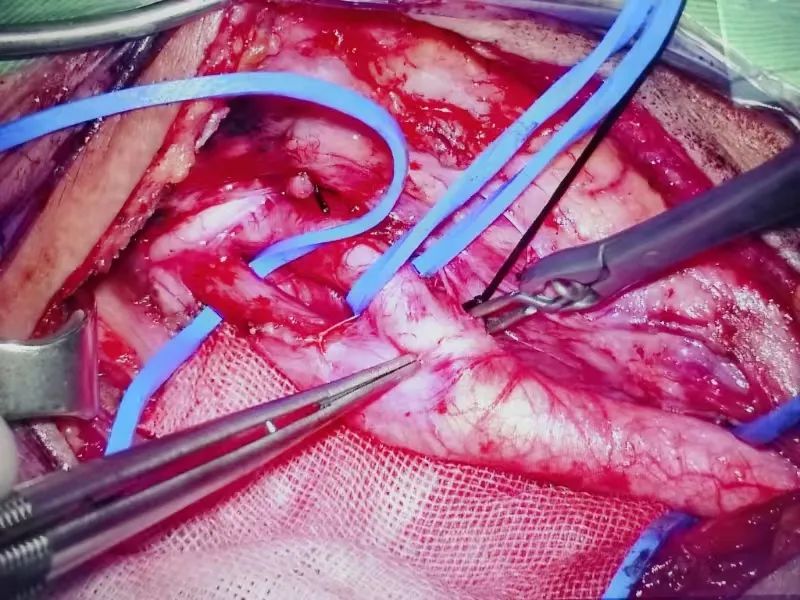

颈内动脉剥脱患者的经历,便是个性化治疗的有力见证。这位患者辗转多家医院,被诊断为颈内动脉狭窄,来到淮南东方总院。神经外科医疗中心张德辉院长团队深知手术风险与难度,先为其进行脑血管造影,精准掌握血管病变情况。随后,在全麻下为患者施行颈内动脉剥脱术。手术过程中,医生凭借高超技艺,小心翼翼地操作,避开周围复杂的神经和血管,将颈内动脉斑块完全剥离,术后颈内动脉血流再通良好。

术后,患者恢复良好,重新回归正常生活,脸上再次绽放笑容。